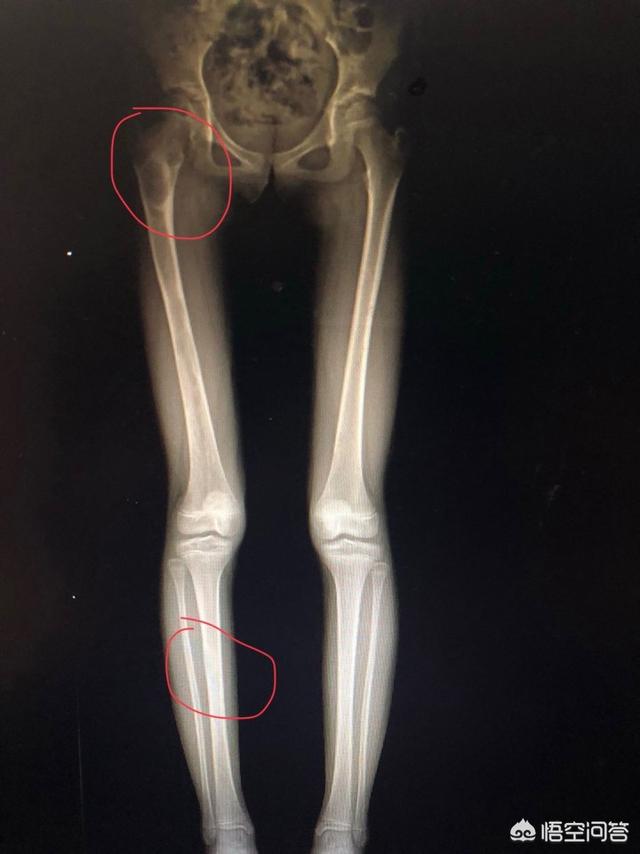

症例2:これは本当に見逃し診断に近い。40歳の中年の兄、脚の痛み。既往歴を聞き、身体をチェックしたところ、軽い筋緊張と感じた。しかし、患者は下肢の全身のX線フィルムを撮るように言った。理由は、彼の友人がリハビリをしていて、彼の下肢の長さが同じでないと言ったので、彼に同じ長さにインソールパッドを高くする説明を繰り返したが、効果がなく、OK、撮影した!その結果、次の番号はまだ彼の、彼の娘は5歳ですが、より強力な、何の違和感もなく、また、彼の友人は靴のインソールを行うために言った、再び繰り返される説明は無効です、OK、撃つ!

大人は大丈夫、子供は下肢の多発性線維性過誤腫、良性腫瘍、ニアミス!患者が大丈夫だと言っても、医師は行われた検査を見る。これは予防的な改善メカニズムでもある。